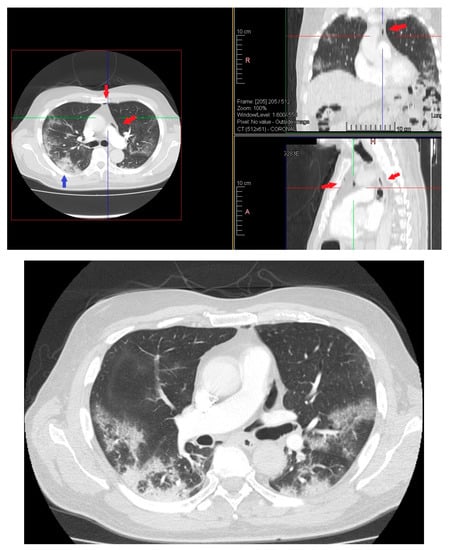

On day 12 computed tomography scan (CT) performed due to elevation of the dimer D at blood test revealed small layer of pneumomediastinum bubble with an increase in consolidation component without any clinician symptoms (Figure 3).

Figure 3. HRTC performed on day 12 showing pneumomediastinum bubble (red arrows) and increase in consolidation component (blue arrow). Detail of HRTC performed on day 12 with small layer of pneumomediastinum bubble.